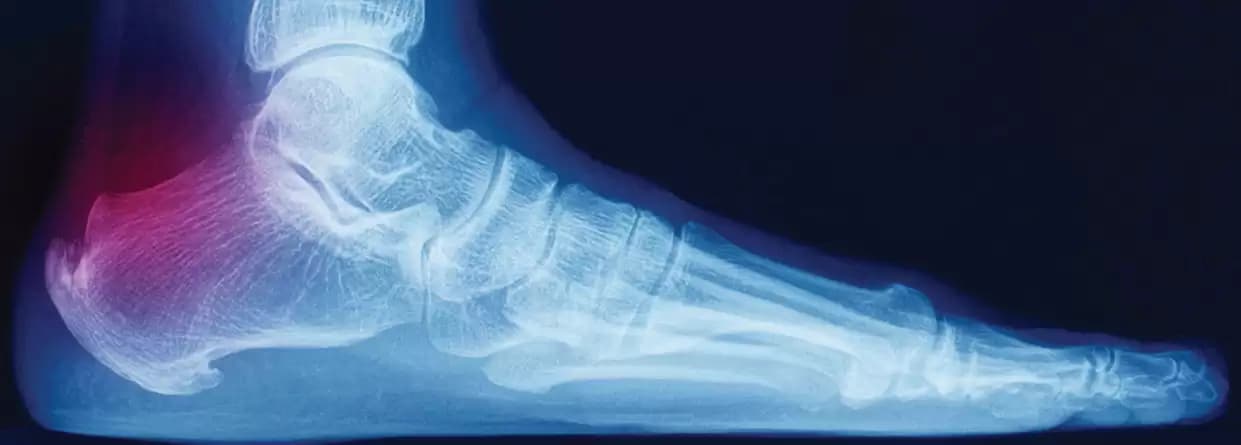

Your doctor might order imaging tests as it helps in revealing structural and tissue information within the foot.

So, they might order an X-ray or MRI test for identifying the heel pain causes such as a bone fracture. However, these tests do not help get a complete look at soft tissues but still are useful to rule out any chances of bone fractures, heel spurs, and other probabilities. With MRI, it becomes easier for the doctor to identify if the plantar fascia has thickened or if there is swelling in the tissues.